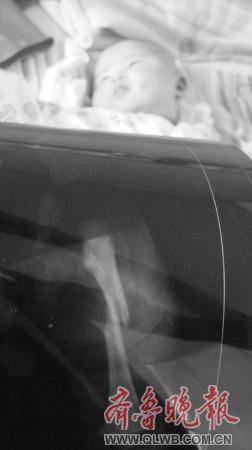

图:拍片显示婴儿右腿骨折。摄影鲁超国

奇奇的爸爸韩先生向记者讲述了婴儿出生时的情景:7月29日傍晚,他在产房外幸福而焦急地等待着孩子的降生。晚上8时许,接生大夫出来了,他高兴地询问母女情况如何,“大夫说孩子的右腿有点问题,我的心一沉,赶紧让大夫把孩子抱过来看看,结果我发现女儿的右腿红肿很厉害,张着嘴‘哇哇’哭个不停。”韩先生当时不明白怎么回事,求医生赶紧为孩子医治。结果拍片之后,婴儿竟然是右腿骨折。